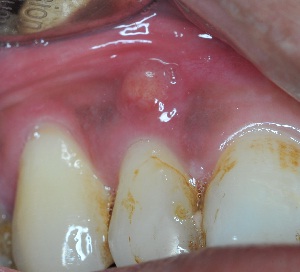

長牙瘡是因口腔組織受細菌感染而發炎,膿液積聚,形成腫脹現象。

圖中所見是牙齒附近長有牙瘡。